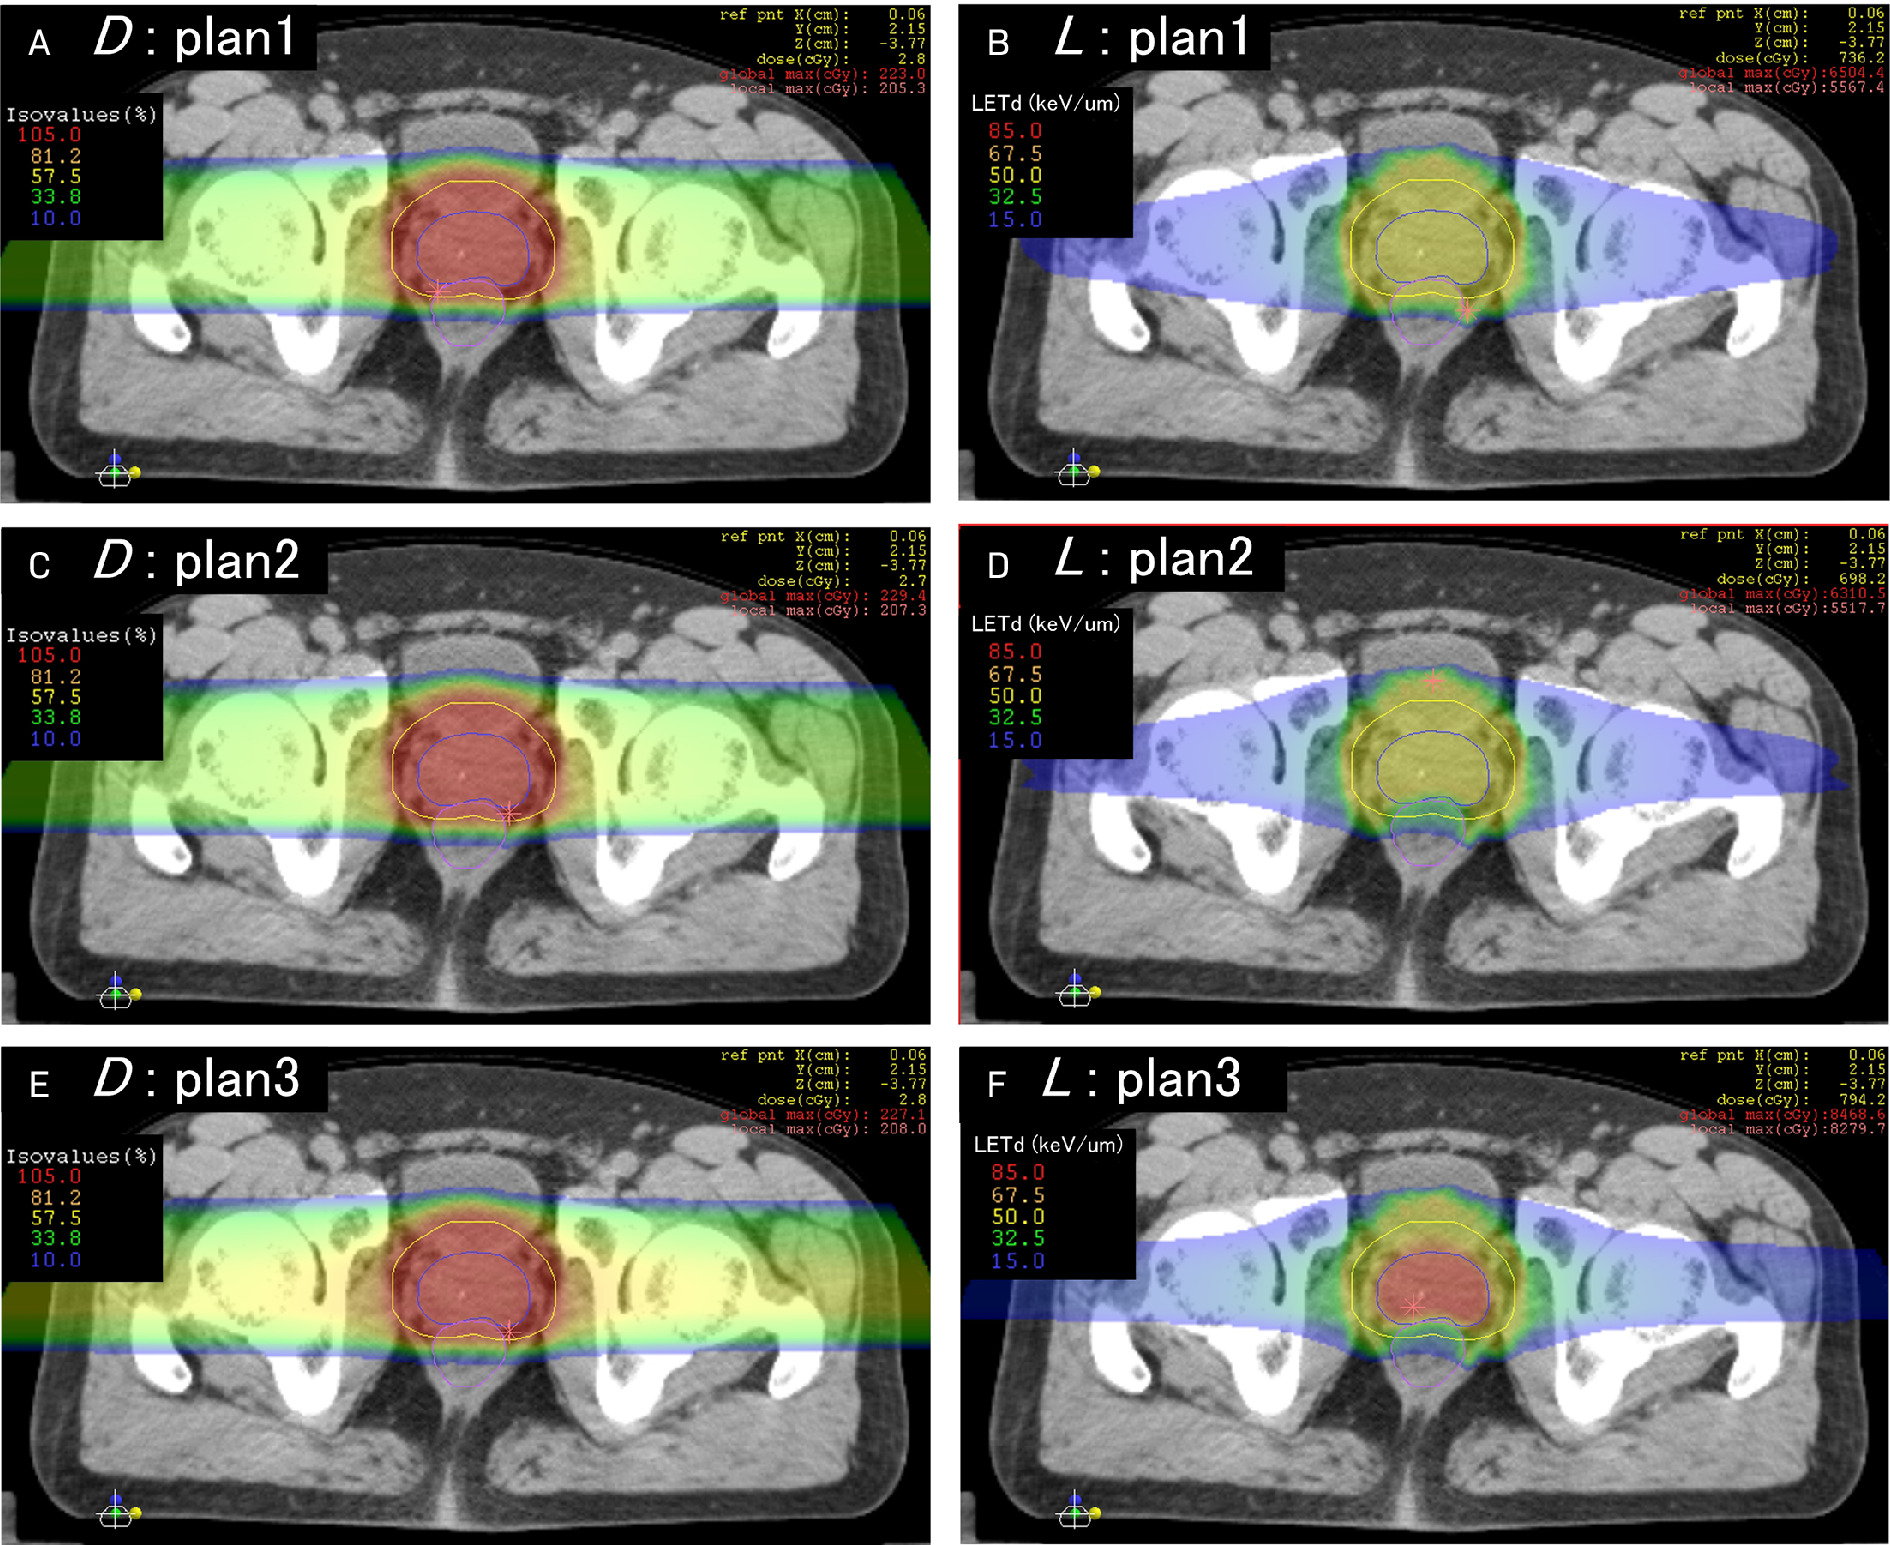

Apart from protons and carbon ions already established in clinical use, research has been done on other species, including helium, lithium, oxygen, and neon ions. 10,13-19 Clinical helium ion therapy has commenced at the Heidelberg Ion Therapy Center (HIT, Germany), with clinical oxygen ion therapy under development. 20 Mayo Clinic Florida likewise plans to attain capacity for combination heavy ion therapy. Unlike other oncologic therapies, HPT offers modularity in dose distribution and potency, facilitating the individualization of therapeutic prescription, including at the level of intra-tumor heterogeneity. 21-24 Even before the clinical availability of multi-ionic radiation therapy (MIRT), the intensity-modulated composite particle therapy (IMPACT) and spot-scanning hadron arc (SHArc) models at the National Institute of Radiological Sciences (NIRS, Japan) and HIT, respectively, have been validated in Monte Carlo simulation for multi-ion treatment planning using LET painting and direct LET-based optimization extended to cover treatment with any combination of protons, helium ions, carbon ions, oxygen ions, and neon ions (Figure 1). 4-6,25-31 The greater the variety of LET spectra from different ions for treatment, the steeper the achievable LET gradients, the less the LET delivered to one voxel forces the LET range deliverable to adjacent voxels. Improved conformality of LET distributions to irregularly shaped targets such as those delineated by functional imaging enables painting of LET gradients onto planning imaging at will. 3-5,10,13,31 Preclinical and clinical studies of MIRT are summarized in Table 1.